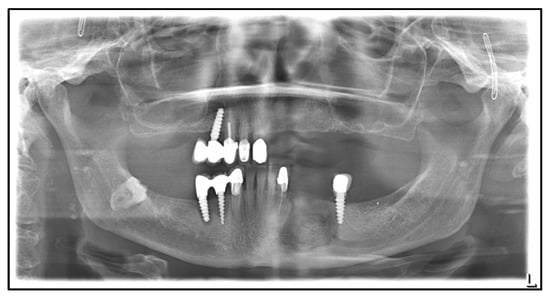

| April 2020: | Partial mandibular resection from the left to the right mandibular angle, CAD/CAM-assisted reconstruction using a free fibular graft and PSI, temporary tracheostomy. In the course: development of aspiration pneumonia treated with piperacillin and tazobactam 4.5 g for 8 days. |

| April 2021: | Placement of four dental implants in the neo-mandible for dental rehabilitation. |